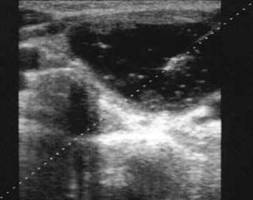

Femeie de 46 ani.Tumefactie voluminoasa a lobului stang, marcant hipoecogena, cu intarire posterioara, de 28x29x29mm (12 cc), cu echouri in interior si microcalcificari parietale.

Citoaspiratia: chist coloid.